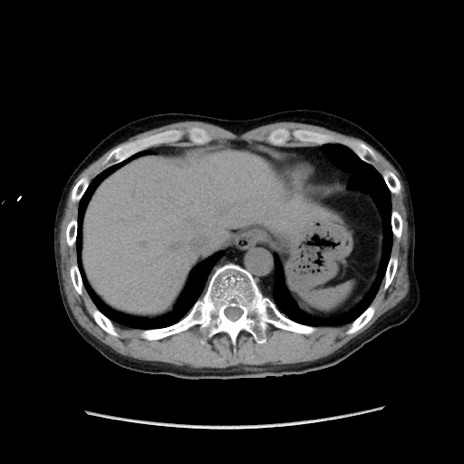

症例37(横断像)

【症例】40歳代 男性

【主訴】腹痛

【現病歴】4時間ほど前に電車に乗車中に臍部上より腹痛出現。徐々に増悪し起立困難となり、救急外来受診。生ものは数日食べていない。今朝お雑煮を食べた。

【身体所見】BT 36.8℃、BP 117/84mmHg、HR 91/min、SpO2 97%、苦悶様、腹部:臍上部広範囲圧痛あり、反跳痛±

【データ】WBC 8100、CRP 0.03